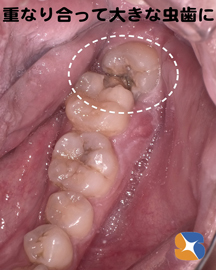

30代の男性。主訴は「奥の親知らずに大きな穴が空いている。かかりつけ医院では、『アゴ骨の神経が近くにあるので抜けない』と言われた。顎関節症なので、長時間、口を大きく開けるのが難しい。虫歯の痛みがひどくなる時があるので、なんとかお願いします。」

Dr:「横向きに生えている親知らずと隣り合わせの歯が重なり合い、そこに食べ物が挟まり続けて虫歯になったようです。

〈レントゲン画像〉横向きに生えている親知らずの歯と重なりあっている所に食べ物が挟まり、きつい痛みを伴う大きな虫歯になりました。